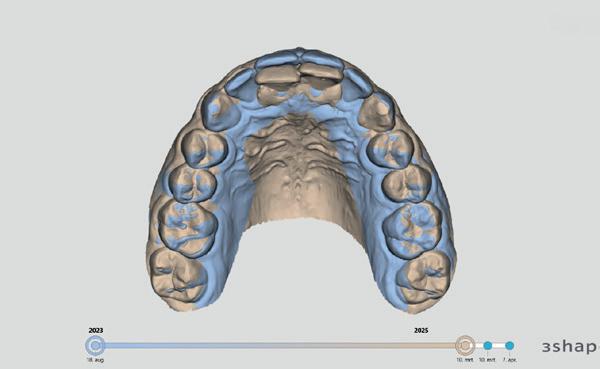

Tijdens het uitvoeren van het onderzoek leek alsof elementen 11 en 21 geen mobiliteit vertoonden en tegelijkertijd was het duidelijk dat ze niet in de juiste positie stonden. In een dergelijk geval, waarbij enige druk nodig is om te reponeren, is het fijn om te weten waar de elementen horen te staan. Het niet in de juiste positie brengen kan zorgen voor een (blijvend) suboptimaal resultaat of een extra lang behandeltraject. Op het moment dat ik bezig was met de vraag ‘Waar horen ze te staan?’, zag ik onze intra-oraal scanner staan en toeval wilde dat er al snel een scan uit 2023 aanwezig was. Deze was gemaakt net na het

afronden van orthodontische behandeling en derhalve een ideale vergelijking. Door een tweetal scans te vervaardigen en deze te matchen, wat ongeveer 3 minuten in totaal kost, kon ik in kaart brengen wat de afwijking was (afbeelding 6-7).